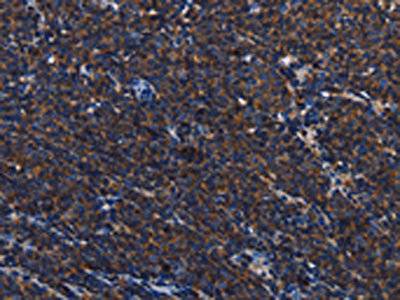

The image on the left is immunohistochemistry of paraffin-embedded Human Lymphoma tissue using CSB-PA480713(PTPRC Antibody) at dilution 1/40, on the right is treated with synthetic peptide. (Original magnification: ×200)